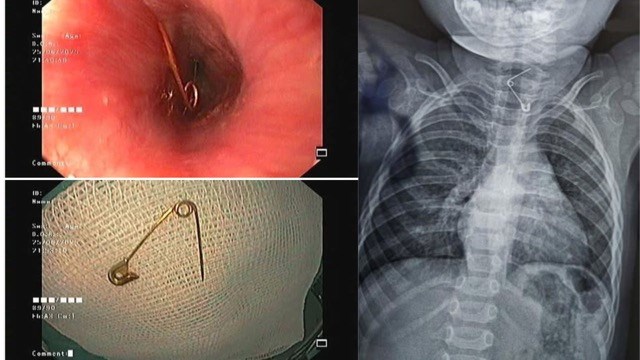

Cháu bé 1 tuổi nuốt kim băng đã bung đầu nhọn ghim vào thành thực quản. Ảnh: Bệnh viện cung cấp.

Tại khoa Cấp cứu, các bác sĩ tiến hành thăm khám và nội soi khẩn cấp. Kết quả cho thấy cây kim băng đã bung ra hình chữ L, đầu nhọn ghim vào thành thực quản gây nguy cơ thủng, xuất huyết và nhiễm trùng nặng. Đây là tình huống đòi hỏi xử lý nhanh chóng, chính xác và cẩn trọng để bảo vệ tính mạng và sức khỏe của bệnh nhi.

Tiếp đó, ê-kíp liên chuyên khoa gồm Tiêu hóa - Tai Mũi Họng - Ngoại khoa, Bệnh viện Nhi đồng 2 TpHCM được huy động để hội chẩn và triển khai phương án can thiệp. Sau quá trình xử lý nội soi tỉ mỉ, các bác sĩ đã lấy được dị vật mà không cần phẫu thuật mở. Nhờ sự phối hợp nhịp nhàng giữa các chuyên khoa, ca cấp cứu đã diễn ra an toàn, bé được cứu khỏi một tình huống nguy hiểm.